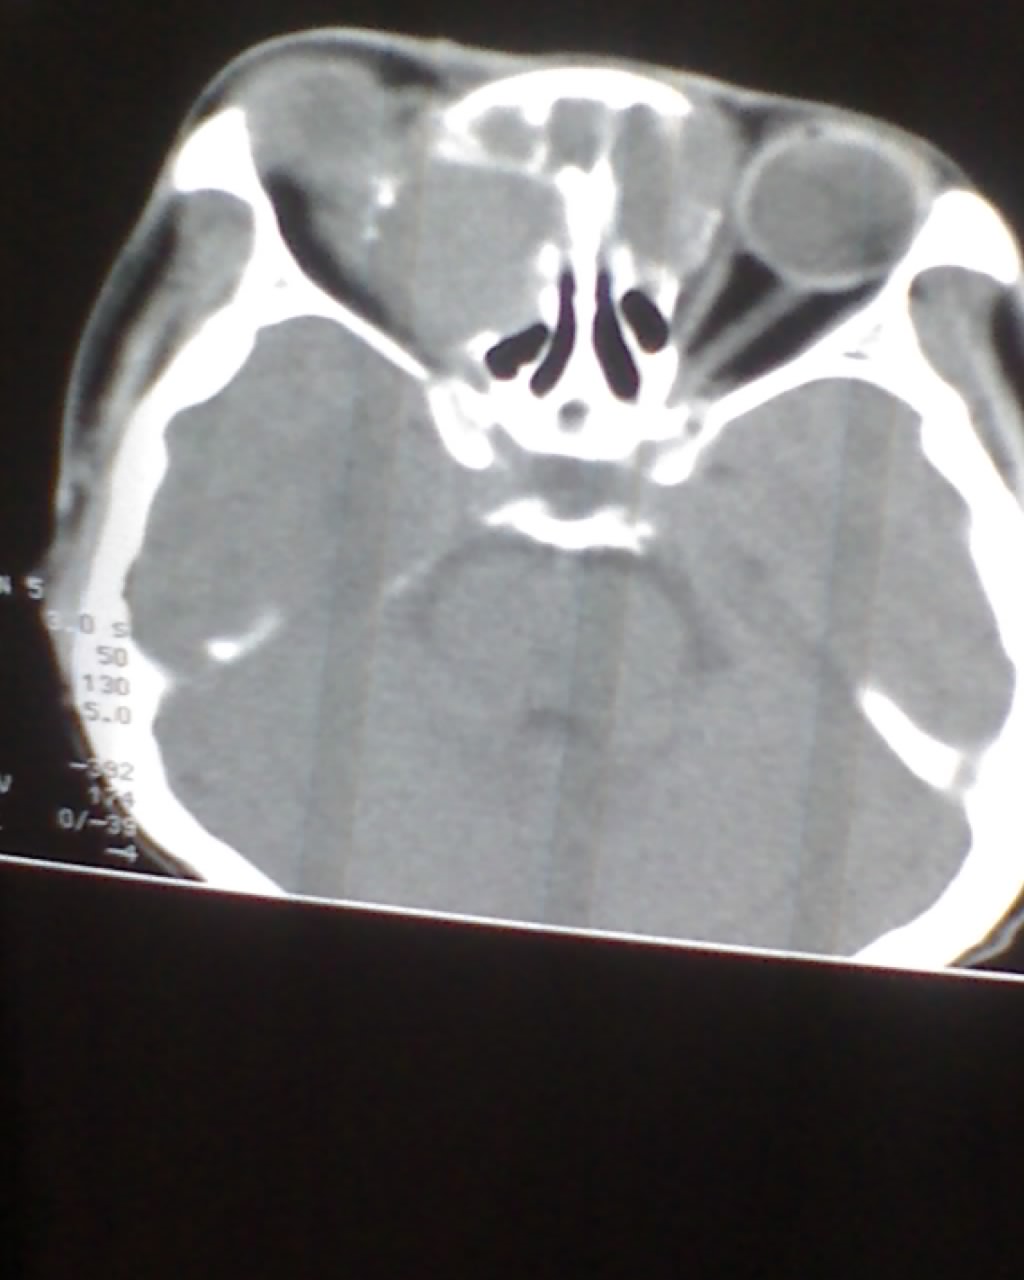

女,45岁,右眼突出,视力模糊来诊。

双侧筛窦可见软组织影充填,筛板破坏,肿块突向双侧眼眶内,以右侧为明显,右侧眼球向前外推压,右视神经稍外移。

考虑良性病变,内翻乳头状瘤可能性大,不除外息肉等。

考虑良性病变,内翻乳头状瘤可能性大,不除外息肉等。支持!(病灶明显起源于鼻窦,呈膨胀性生长,周边骨质吸收 破坏)。

双侧额窦,筛窦可见软组织影充填,筛板破坏,肿块突向双侧眼眶内,以右侧为明显,右侧眼球向前外推压,右视神经稍外移。

考虑良性病变,黏液囊肿可能性大,不除外内翻乳头状瘤等,建议强化.前者不增强.